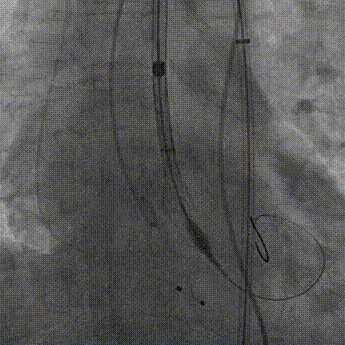

彭小平教授 南昌大学第一附属医院 不断探索医疗可能,筑牢患者长期保障 TAVR 治疗的终极目标,不仅是完成一次手术,更是为患者构建长期稳定的生命保障,而瓣膜耐久性是直接关乎患者后期是否需要二次手术的关键所在。全球首款预装干瓣的问世,为临床提供了全新的选择方案。厂家的15 年质保承诺,是源于材料研发的突破与临床验证的底气。从临床角度,如未来瓣膜可以耐久15年,则可大大减少患者反复就医的身心负担与经济压力,本质上是为患者的长期健康 “投保”。 人生的每一次选择,都需要慎重。相信在行业的前行中,我们不断探索医疗的可能性,让每一次治疗都能真正护航患者长远健康! 患者病史 主诉与现病史:3 年前开始出现胸闷、气促,活动后(如上楼、上坡)症状加重,休息后可缓解,当地医院心脏彩超提示主动脉瓣狭窄,未予特殊治疗;2 年前发现血压轻度升高,口服阿奇沙坦片(40mg,每日 1 次)降压,血压控制尚可;近 1 个月胸闷气促症状明显加重,2025 年 10 月 13 日外院心脏彩超提示主动脉瓣重度狭窄,为进一步诊治入院。 既往史:高血压病史 2 年,规律服用阿奇沙坦片(40mg qd);1 年余前因外伤致腰椎骨折,保守治疗后痊愈;有慢性阻塞性肺疾病病史;有胃窦糜烂、十二指肠球部溃疡史,2023 年曾发生急性上消化道出血;有真菌性食管炎、多发性结肠息肉病史。 术前超声提示:主动脉瓣钙化,主动脉瓣狭窄(重度),左室肥厚,升主动脉增宽。 二尖瓣反流(轻度),三尖瓣反流(轻度),肺动脉瓣高压(轻度)。 左室舒张功能减低,收缩功能正常,左室射血分数 74.7%。 术前CT:Type0型二叶瓣,瓣叶增厚并极重度钙化,钙化主要分布在瓣叶基底部,延伸到左室流出道。主动脉瓣环径24.8mm;升主动脉狭窄后扩张至主动脉弓,双侧瓣叶开口高度可,窦部空间可,STJ内径增宽,升主动脉内径可,预估冠脉低风险;主动脉水平夹角49.1°,非横位心;主动脉弓角、弓距可;“自杀左室”,建议术前补液,ECMO湿备,术中注意循环崩溃。 外周双侧入路内径可,髂总动脉有零星散状钙化,双侧股动脉均能通过20F大鞘,右股低分叉。 手术策略:推荐使用右侧股动脉为主入路,左侧股动脉为辅助入路;右股分叉上方1cm穿刺;推荐使用18mm球囊预扩,预装AV23瓣膜。 手术过程:在右股动脉穿刺建立通路后,顺利送入大鞘,经食道超声及血管造影确认路径稳定。18mm球囊预扩后评估冠脉灌注良好,后将Prostyle A® AV23瓣膜精准释放于目标位置,20mm球囊后扩,超声显示轻微瓣周漏,术后即刻造影显示无明显反流,峰值压差由术前的80mmHg降至12mmHg,心功能明显改善,患者生命体征平稳。 18球囊预扩无腰无漏 输送器跨瓣顺利 定位 平稳释放瓣膜 20球囊后扩 最终造影,位置良好,轻微瓣周漏 Prostyle A®预装干瓣——助力临床最优化解决方案 1、流入端桶状设计:流入端桶状的设计,锚定迅速,有效减少释放步骤,提升植入稳定性; 2、平衡的收腰设计:二叶瓣小心室患者对瓣膜径向支撑力提出更高要求,Prostyle A®均衡的收腰设计可更好适应小瓣环及不规则瓣口结构,保证了EOA,有效降低了循环崩溃风险,提高瓣膜的耐久性; 3、预装干瓣 便捷顺安:金仕生物专利抗钙化技术运用纳米技术去除组织内的细胞碎片和磷脂,封闭游离醛基,从根本上阻断了瓣膜钙化的多项因素,显著提升了瓣膜的耐久性;同时,相比较传统戊二醛保存方式,干式存储最大限度的保留心包的亲水亲油平衡,还原组织天然曲柔性,进一步保障了瓣叶开合,保证长期耐久性; 专家简介 彭小平 南昌大学第一附属医院(点击查看专家详细简历) · END ·